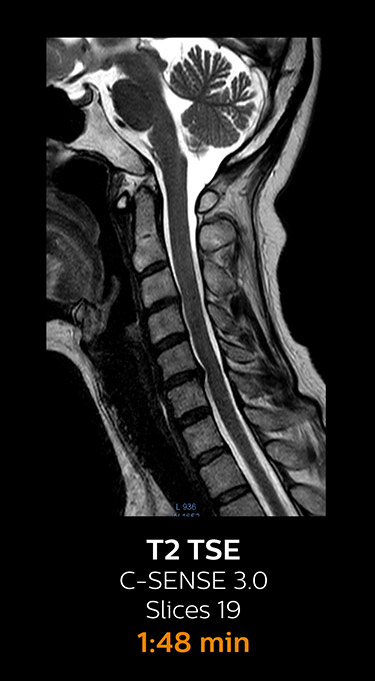

Fast MRI of cervical spine

With Compressed SENSE, the scan time for the routine cervical spine examination at KNC was reduced from 13:11 to 9:52 minutes, which corresponds to 25% reduction.

MRI examination of cervical spine with Compressed SENSE

MRI examination of the cervical spine with Compressed SENSE

Ingenia 3.0T CX

Scan time 9:52 min. (was 13:11 min. without Compressed SENSE)